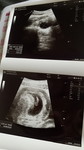

เราเคยฝันเห็นเจ้าแม่กวนอิมบ่อยๆตอน5-10wแพ้ท้องหนักมาก ป่วยหนัก +กับเราไปทำบุญวัดนั้นบ่อยมากช่วงนั้นในใจคงนึกว่าไปบ่อยเลยเก็บมาฝัน จนไปอัลตราซาวด์หมอแจ้งว่าน่าจะเด็กผู้หญิงแต่ไม่100% ผ่านมา3-4วันเราก็ฝันว่าเจ้าแม่กวนอิมมาบอกเราว่าถ้าได้ลูกสาวตามที่ขอแล้วให้ไปถวายน้ำให้หน่อย😅😅😅🥹☺️เรื่องบางเรื่องก็แปลกดีจริงๆนะคะแม่ๆ ไม่รู้ว่าเราตั้งใจพูดขอหรือใจเรานึกขอกันเนอะ 🙏🏻🩷🩷🩷🩷#ท้องแรกคะ #ความเชื่อส่วนบุคคลนะค่ะ #มาเล่าสู่กันฟัง #ลูกตัวยาวมาก5555+